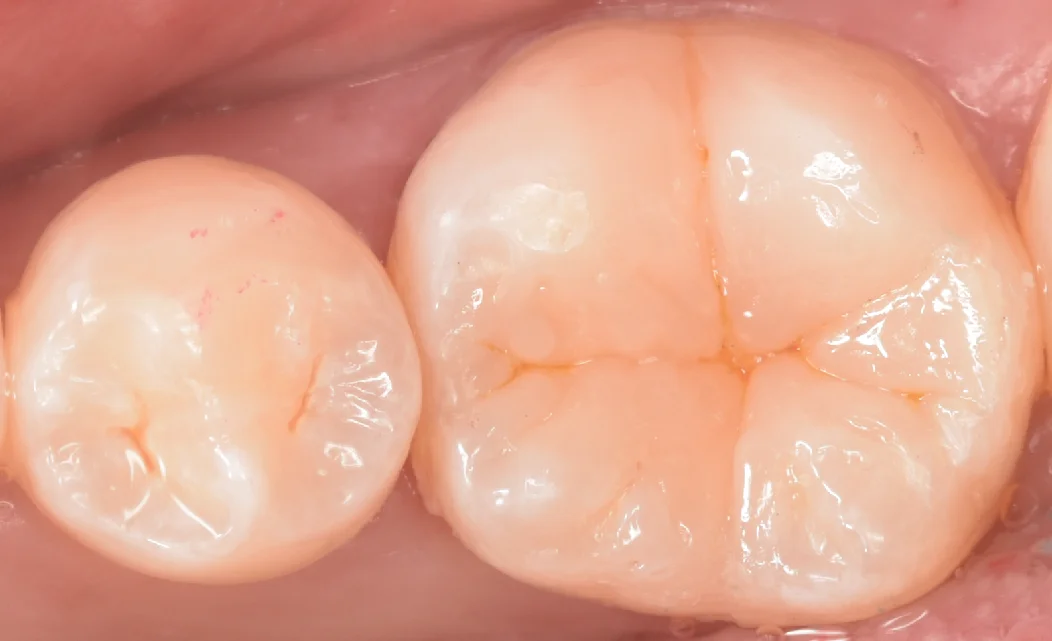

さて、詰め終わったのがこちらになります。

歯の溝の色は前後の歯と合わせておきましたので、色に関しては違和感がなく仕上げられたかと思います。

見た目もデザインについては結構特殊な歯の形をしていたため、やや違和感がありますが、少なくとも元の歯の形をイメージして詰めているので大きくは外していないと思います。

術前術後の比較の写真がこちらになります。